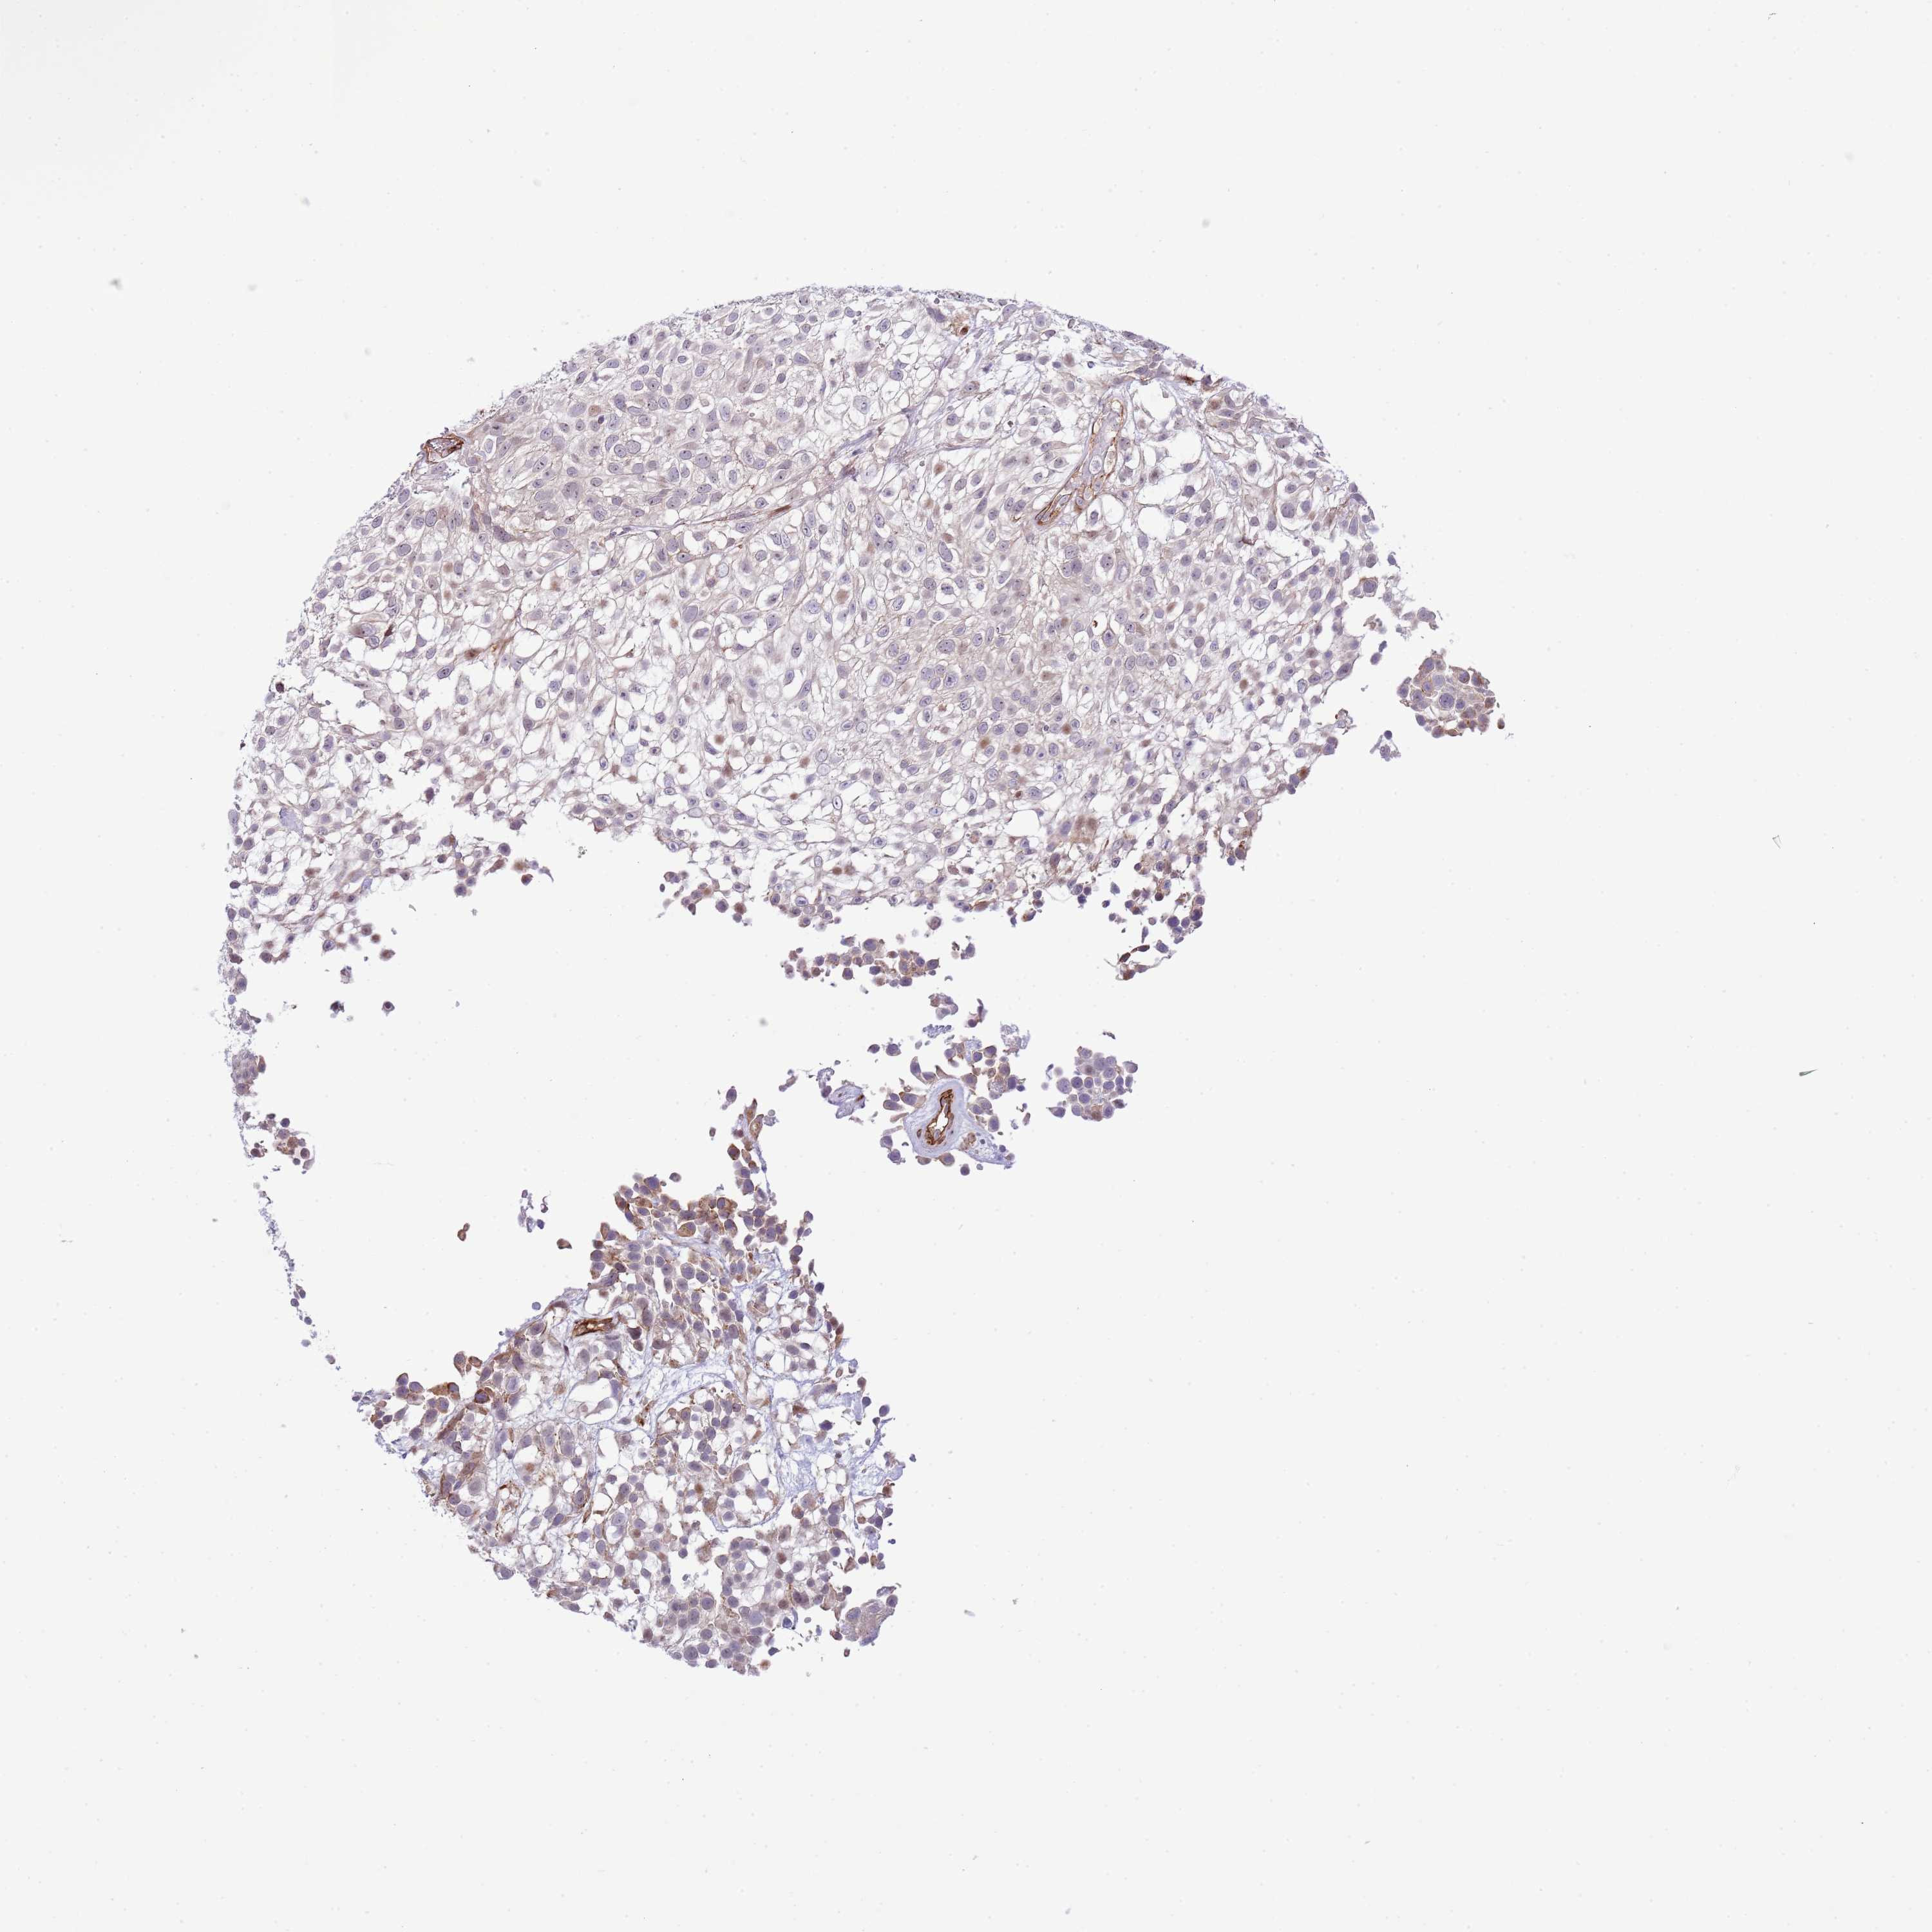

UROTHELIAL CANCER - Protein expressioni

A mouse-over function shows sample information and annotation data. Click on an image to view it in a full screen mode. Samples can be filtered based on level of antibody staining by selecting one or several of the following categories: high, medium, low and not detected. The assay and annotation is described here.

Note that samples used for immunohistochemistry by the Human Protein Atlas do not correspond to samples in the TCGA dataset.

Antibody stainingi

Antibody staining in the annotated cell types in the current human tissue is reported as not detected, low, medium, or high, based on conventional immunohistochemistry profiling in selected tissues. This score is based on the combination of the staining intensity and fraction of stained cells.

Each image is clickable and will lead to virtual microscopy that enables deeper exploration of all samples and also displays staining intensity scores, fraction scores and subcellular localization as well as patient and tissue information for each sample.

Antibody HPA019062

Antibody HPA043230

Staining

High

Medium

Low

Not detected

Intensity

Strong

Moderate

Weak

Negative

Quantity

>75%

75%-25%

<25%

None

Location

Nuclear

Cytoplasmic/membranous

Cytoplasmic/membranous,nuclear

Urothelial carcinoma, High grade

Urothelial carcinoma, Low grade